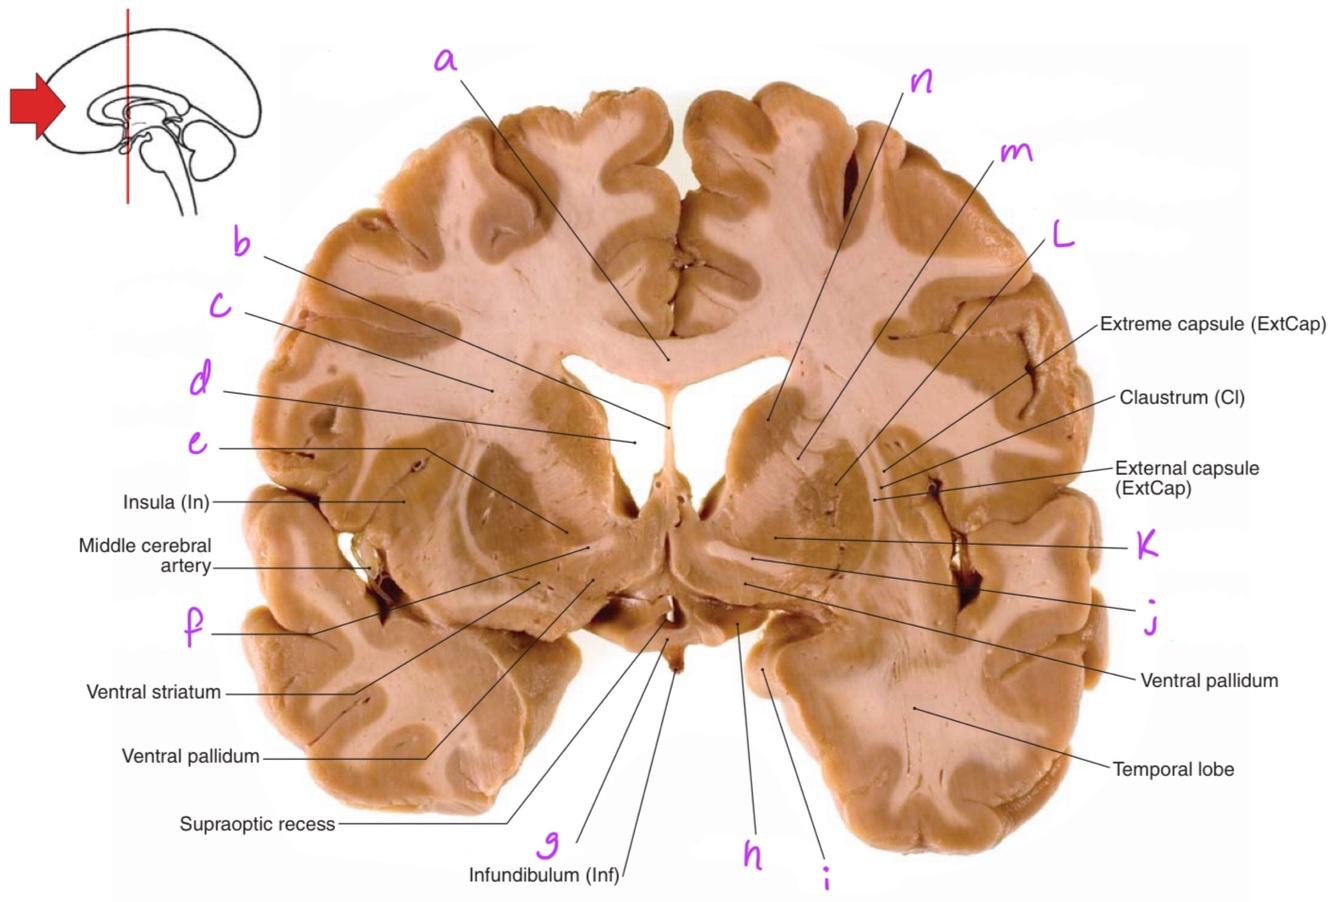

9

Q

a

Body of corpus callosum

10

b

septum pellucidum

11

c

Corona radiata

12

d

Anterior horn of lateral ventricle

13

e

Globus pallidus

14

f

Anterior commissure

15

g

Optic chiasm

16

h

Optic tract

17

i

Uncus

18

j

19

k

20

L

Putamen

21

m

Anterior limb of internal capsule

22

n

Head of caudate nucleus